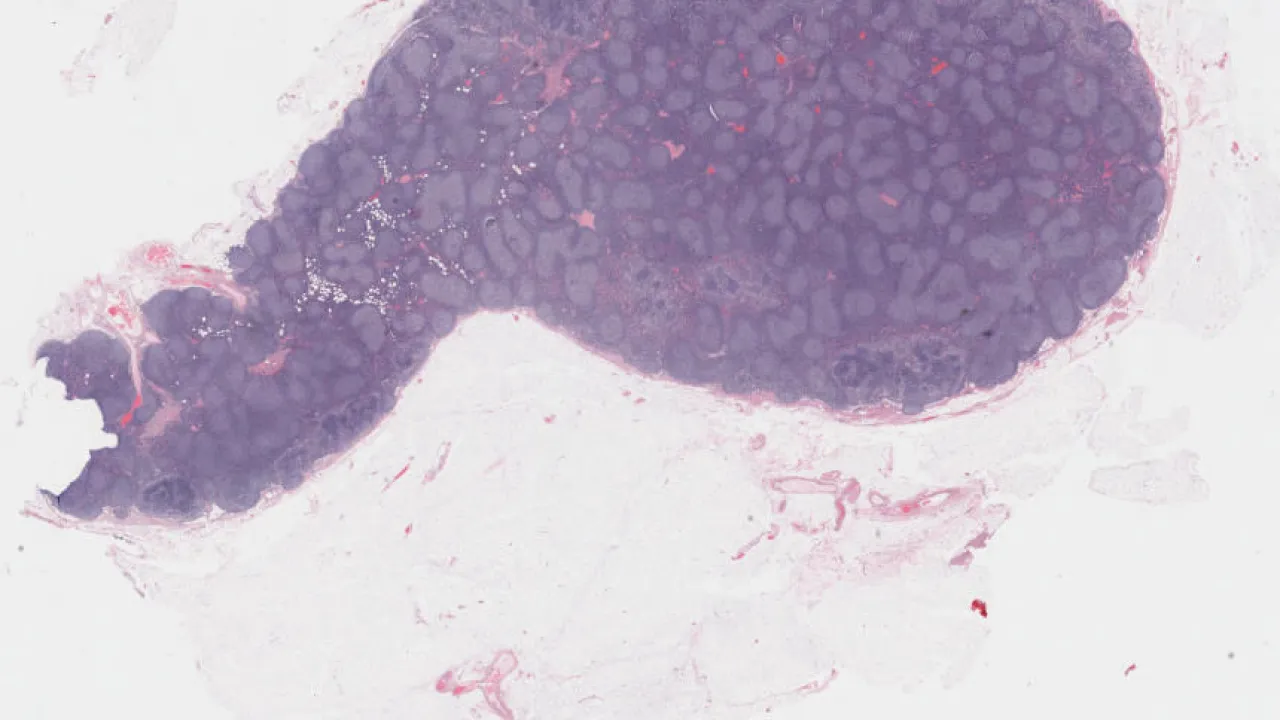

Lymph node, follicular lymphoma